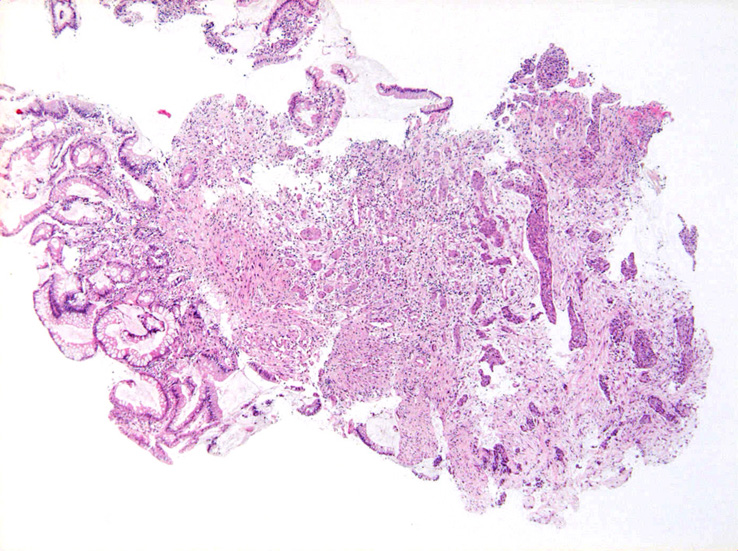

S状結腸粘膜生検組織所見:

粘膜筋板直下に小型胞巣を作って浸潤し炎症性の間質をともなう。 浸潤性増殖のわりに細胞は均一, そんなに異型性も強くない。apoptosisに陥った細胞が散在する。部位によっては胞巣状増殖細胞は細胞間橋がありそうな扁平上皮様に見える。深いところは線維性間質が増えてきて細胞は索状となりcarcinoidなども鑑別候補となるかもしれない。明らかな腺管形成, 粘液産生はみられない。35歳男性, わりとおとなしい扁平上皮癌様の組織か?と生検初見時に考えられた。desmoplasticな間質にもよく観察するとバラけた細胞異型が認められる。 (腫瘍胞巣①, ③)